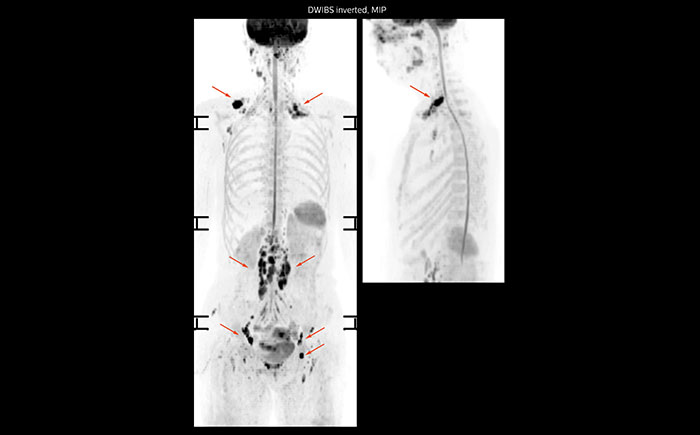

Whole body diffusion

A 61-year-old female with a malignant lymphoma underwent an MRI exam with whole body diffusion weighted imaging (DWIBS) as well as PET. On the images shown, the resolution of DWIBS is better than PET, which allows visualization of the small pelvic lesions and almost no distortion is seen in the neck area.

Whole body diffusion

A 61-year-old female with a malignant lymphoma underwent an MRI exam with whole body diffusion weighted imaging (DWIBS) as well as PET. On the images shown, the resolution of DWIBS is better than PET, which allows visualization of the small pelvic lesions and almost no distortion is seen in the neck area.